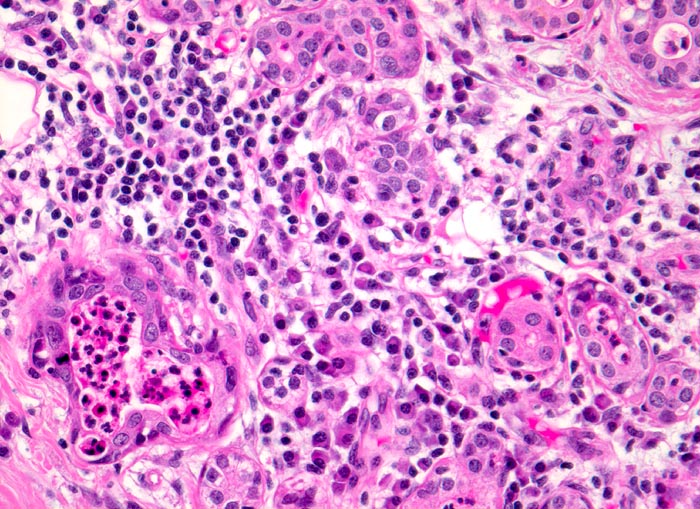

Akute Sialadenitis

Parotis

Akute bakterielle Sialadenitiden werden oft verursacht durch eine Gangobstruktion (z.B. Steine), können aber auch bei schlechter Mundhygiene oder bei Immunsupression vorkommen. Die Feinnadelpunktion kann durch eine Druckverminderung zu einer Schmerzreduktion führen. Das Punktat gleicht einem Abszess mit neutrophilen Granulozyten, Fibrin und Nekrosen. Gelegentlich sind Erreger nachweisbar. Zu einem späteren Zeitpunkt kommen Lymphozyten, Plasmazellen, Makrophagen, Granulationsgewebe und Epithelien mit regenerativen Veränderung/Atypien zur Darstellung.